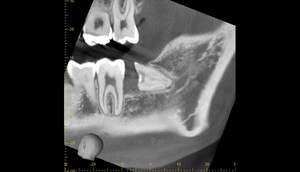

CT画像②

麻布十番歯科での右下の親知らずが真横に生えている症例のCT画像②

CTの1部分の画像です。下歯槽神経と親知らずはほんの少し接触しているような状態でした。リスクなど説明し、2回法で抜いていくことにしました。

2回法とは、その名の通り、2回かけて親知らずを抜いていく方法になります。

1回目は歯の頭の部分だけを切るだけになります。2回目は数ヶ月経ってから行いますが、1回目で頭の部分を取ったスペースに歯が伸びてきますので、下歯槽神経と離れたかを確認してから、根の部分を抜いていく、そういった方法になります。